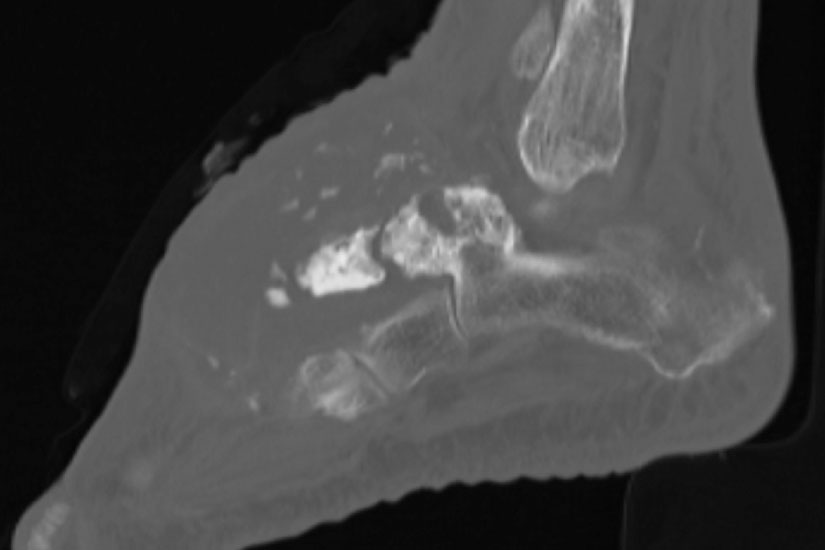

Die Computertomographie (CT) wird seltener als die MRT herangezogen um eine spezi­fischen Artdiagnose zu finden, liefert aber wertvolle Informationen zur Kortikalis­beschaffen­heit (Kontinuität, Stärke, enostale Arrosion) unterschiedlichster Knochenläsionen. Insbe­sondere die enostale Kortikalisarrosion, wie sie häufig bei chondrogenen Tumoren anzu­treffen ist, kann konkrete Hinweise liefern, die in Zusammenschau mit histologischen Befunden zu einer definitiven Diagnose führen (siehe Spezifische Entitäten: Enchondrom vs. atypischer chondrogener Tumor/Chondrosarkom). Die Computertomographie ist außerdem hilfreich in der Abgrenzung komplexer anatomischer Strukturen (z.B. 3D-Rekonstruktion) und sehr kleiner Knochenläsionen. Bei der Diagnose des Osteoidosteoms bleibt die CT Mittel der Wahl um die charakteristischen Veränderungen in der bildgebenden Diagnostik exakt darzustellen (Abb. 6). Die Gewebedichte von weichteiligen Tumoren, insbesondere von intra- und extraossären Lipomen, kann im Vergleich zum subkutanen Fettgewebe mithilfe der Houndsfield-Skala beurteilt werden.

Davon abzugrenzen sind tumor-ähnliche Läsionen (tumor-like lesion) bzw. Pseudotumoren. Eine strikte Differenzierung zwischen diesen beiden Begriffen ist nicht möglich, allgemein gültige Definitionen für diese Begriffe existieren nicht. Generell bieten tumor-ähnliche Läsion und Pseudotumoren zwar den klinischen und zum Teil auch radiologischen Aspekt einer echten Neoplasie, nicht aber das biologische Verhalten. Konkret werden hierzu u.a. Ganglien (intraossär und weichteilig), Fremdkörpergranulome (weichteilig), aber auch akzessorische Muskeln (z.B. M. soleus accessorius, Abb. 1) und Abszessformationen 12 gezählt. Andere Vertreter dieser Art, insbesondere am Fuß lokalisiert, beinhalten u.a. Warzen und Hyperkera­tosen aber auch das Morton-Neurom oder die Plantarfibromatose (M.Ledderhose) (Abb. 2). Sehr seltene, aber gehäuft am Fuß zu findende Pseudotumoren beinhalten die Tumoröse Kalzinose 3 und die Melorheostose, die an dieser Stelle nur beispielhaft genannt werden sollen. Die Tumoröse Kalzinose beruht auf einer Störung des Kalzium- und Phosphat­haus­halts und zeigt eine Prädilektion für mechanisch stark belastete Regionen 4 (Abb. 3). Bei der Melorheostose handelt es sich um eine gutartige Kortikalisverdickung mit unregel­mäßigen Hyperostosen entlang einer Extremitat (Abb. 4). Die Ätiologie der auch als Kerzen­wachskrankheit bezeichneten, meist monomelischen Veränderung ist unklar (Knöller, 2002).